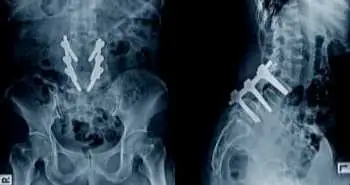

This randomized, double-blind, controlled clinical trial after lumbar interbody fusion was conducted to assess (a) Whether multimodal analgesia lower VAS (visual analog scale) pain scores by a clinically important amount (b) Does this analgesic approach minimize the amount of morphine patients consume after their surgery (c) Is this technique linked with fewer opioid-related side effects after surgery.

This study recruited 80 adult patients undergoing lumbar interbody fusion. The participants were randomly assigned into two groups: (1) Control group (n = 40) who received infiltration of the surgical incision at the end of the procedure with an injection of epinephrine 0.5 mg (0.5 mL) and 0.5% bupivacaine 100 mg (20 mL) (2) Multimodal group (n = 40), who received wound infiltration with the similar technique but with different medications: ketorolac 30 mg (1 mL), 0.5% bupivacaine 92.5 mg (18.5 mL), morphine 5 mg (0.5 mL), and epinephrine 0.5 mg (0.5 mL).